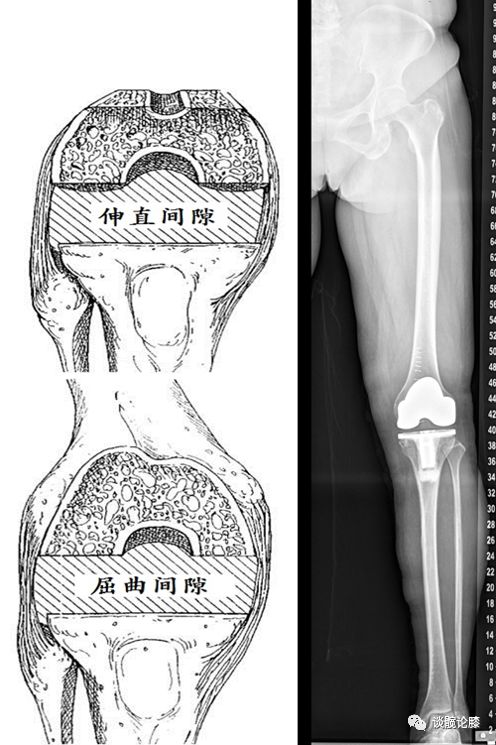

间隙平衡要求

1、最佳:相等矩形的屈伸间隙 ;内外侧间隙无紧张和松弛

2、可接受:内外侧间隙不平衡< 3mm ;内外侧间隙不平衡<3°;关节间隙稍紧 ;屈曲间隙稍松于伸直间隙 ;外侧间隙稍松于内侧间隙

不同截骨技术软组织平衡步骤不同

1、测量截骨技术:先完成胫骨、股骨截骨;再平衡软组织

2、间隙平衡技术:先行胫骨和股骨远端截骨;完成伸直间隙平衡;再行股骨后髁截骨